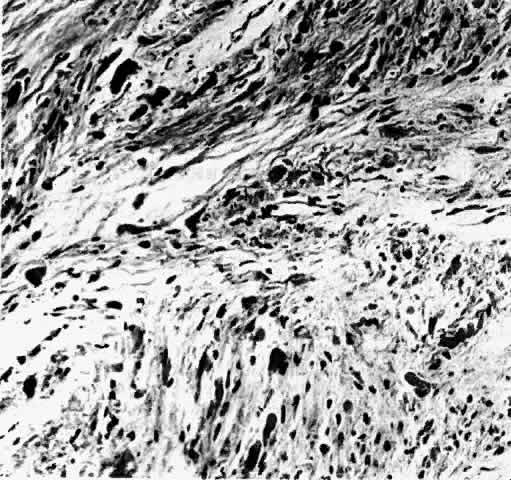

Gross examination of optic nerve gliomas usually reveals a smooth, fusiform, intradural enlargement of the optic nerve (Fig. 6). After extending through the optic canal in a dumbbell fashion, there may be extension to posterior structures.4 Most optic gliomas are classified as juvenile pilocytic astrocytomas and have a benign histologic appearance. Pilocytic refers to the spindle-shaped astrocytes with elongated nuclei that are often arranged in a parallel fashion (Fig. 7). Oligodendroglial cells may be scattered throughout the glioma. These tumors can contain carrot- or cigar-shaped eosinophilic astrocytic cytoplasmic inclusions known as Rosenthal fibers4 (Fig. 8). Microcystoid extracellular spaces containing acid mucopolysaccharide generated by mucin-producing astrocytes are often seen.85 Less common features can include capillary hyperplasia, mitotic figures, tissue necrosis with hemorrhage,86 and glial giant cells.4

Fig. 7. Photomicrograph of an optic nerve glioma, demonstrating a mixture of pilocytic astrocytes and some oligodendro-glial cells.

The histopathologic features of a chiasmal glioma are almost identical to those of an optic nerve glioma. Because the normal optic chiasm lacks the connective tissue septae found in the normal optic nerve, these septae are not found in chiasmal glioma specimens.71 A reactive leptomeningeal hyperplasia may surround gliomas, leading to an erroneous biopsy interpretation of meningioma23 (Fig. 9). In contrast to schwannomas and neurofibromas, which are positive for the intermediate filament vimentin, immunohistochemical analysis of cytoplasmic glial intermediate filaments in pilocytic astrocytomas reveals positive staining for glial fibrillary acidic protein.87

Controversy exists as to whether optic gliomas are hamartomas or true neoplasms. The tumors were first described as hamartomas by Hudson in91 In 1969, Hoyt and Baghdassarian92 supported Hudson's theory and concluded that optic gliomas represented congenital, non-neoplastic tumors with self-limited growth followed by stability. Histologic features and growth rates, however, suggest that optic gliomas are true neoplasms. Burnstine93 evaluated optic gliomas with colloid silver impregnation of nucleolar organizer region-associated proteins (AgNORs) whose size, number, and morphology indicate the pattern of cell proliferation or transformation. Optic glioma AgNOR counts were similar to optic nerve meningiomas and had features consistent with true neoplasms (Fig. 10). In a review of 623 reported cases, Alvord and Lofton2 described optic nerve growth kinetics based on time to recurrence of disease. Growth patterns had variable rates, ranging along a continuum from a simple logarithmic rate to a decelerating growth rate; these rates were not characteristic of hamartomas.

Fig. 10. Colloid silver impregnation of optic nerve glioma demonstrating muliple nucleolar organizer region-associated proteins (AgNORs) in each nucleus. (Burnstine MA, Levin LA, Louis DN et al: Nucleolar organizer regions in optic gliomas. Brain 116:1564, 1993. Reproduced with permission from Oxford University Press.)